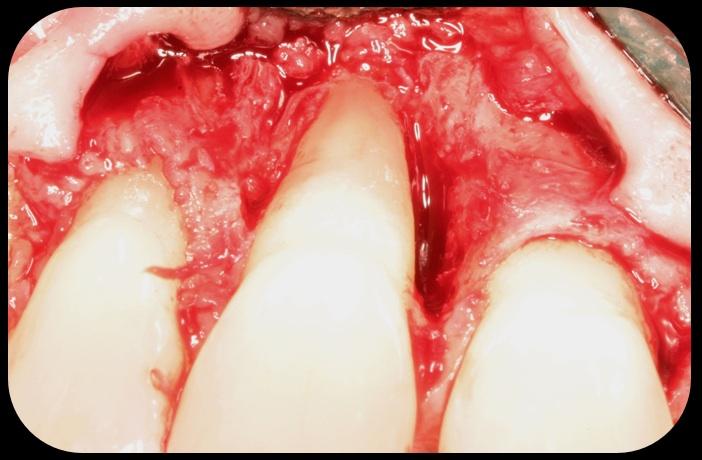

Then, too, are opportunities to prepare the site for regeneration by coupling therapies, applying an enamel matrix derivative, along with traditional bone grafts of demineralized freeze-dried bone allograft; potentially, gains in attachment with minimal probing depth and retained papilla may avoid the need for an implant (Figure 2 through Figure 7).

Facial bone loss and a mesial vertical defect.

Fig. 3

Application of enamel matrix derivative.

Fig. 4

Demineralized freeze-dried bone allograft.

Fig. 5

Evidence of clinical attachment gain.

Fig. 6

The 9-year postoperative radiograph.

Fig. 7